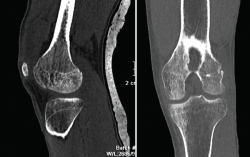

1.1. Fémur (Figuras 18 y 19)

Figura 18. A: corte de reconstrucción coronal; B: axial; y C: reconstrucción 3D de tomografía axial computarizada de rodilla: fractura longitudinal del fémur extendida al techo intercondilar.

Figura 19. Corte de reconstrucción sagital y coronal de tomografía axial computarizada de rodilla: fractura de Hoffa del fémur, del cóndilo femoral externo, de difícil diagnóstico en las radiografías.